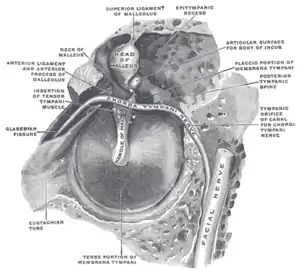

Глазерова щель

Каменисто-барабанная щель (Глазерова щель) — узкое пространство между барабанной частью височной кости и выступающим наружу краем крыши барабанной полости, место выхода барабанной струны из тимпанальной полости[2]. С одной стороны щель открывается на нижнечелюстную ямку, с другой в тимпанальную полость.